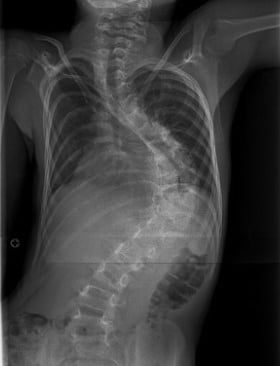

الجنف هو حالة بنيوية تصيب العمود الفقري، حيث ينحني العمود الفقري بشكل غير طبيعي من جانب إلى آخر، وغالبًا ما يصاحبه دوران حول محوره بدلًا من بقائه مستقيمًا عند النظر إليه من الخلف. وقد يأخذ هذا الانحناء شكل حرف S أو C، ويظهر الجنف بشكل أكثر شيوعًا خلال فترات النمو السريع مثل مرحلة المراهقة، إلا أنه قد يحدث في أي عمر.

في العمود الفقري السليم، تُشكِّل الفقرات عمودًا رأسيًا مع انحناءات طبيعية خفيفة من الأمام إلى الخلف. أمّا في حالة الجنف، فإن العمود الفقري ينحني أيضًا بشكل جانبي في المستوى الأمامي، وقد يصاحبه دوران، مما قد يؤدي إلى عدم التناسق في وضعية الجسم والمظهر العام.

ويُؤخَذ تشخيص الجنف عادةً بعين الاعتبار عندما يتجاوز انحناء العمود الفقري حدًا معيّنًا في الفحوصات التصويرية، وغالبًا ما يتم قياس ذلك باستخدام زاوية كوب (Cobb angle) في صور الأشعة السينية.

يبدأ تشخيص الجنف بتقييم سريري يشمل أخذ تاريخ صحي مفصّل وفحصًا بدنيًا شاملًا. وقد يلاحظ الممارس الصحي وجود عدم تماثل في مستوى الكتفين أو الوركين أو الخصر، أو اختلافًا في وضعية الجسم. وتُستخدم الفحوصات التصويرية، مثل الأشعة السينية، لتأكيد وجود الانحناء وقياس درجة شدّته.

في كثير من الحالات، يبقى الجنف الخفيف مستقرًا ولا يسبب أعراضًا ملحوظة. ومع ذلك، فإن الانحناءات التي تتفاقم بمرور الوقت — خاصة خلال فترات النمو السريع — قد تؤثر على وضعية الجسم، والقدرة على الحركة، ومستوى الراحة. أما الانحناءات الشديدة، فقد تؤثر على الوظيفة الميكانيكية للعمود الفقري والأنسجة المحيطة به إذا لم تتم متابعتها وإدارتها بشكل مناسب.